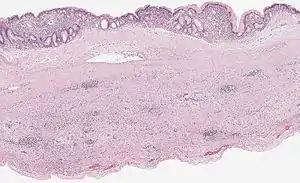

Pancreatic mucinous cystadenoma

Pancreatic mucinous cystadenoma, also known as "mucinous cystadenoma of the pancreas", is a benign tumour of pancreas. It is one of the cystic lesions of the pancreas.[1]

Microscopy